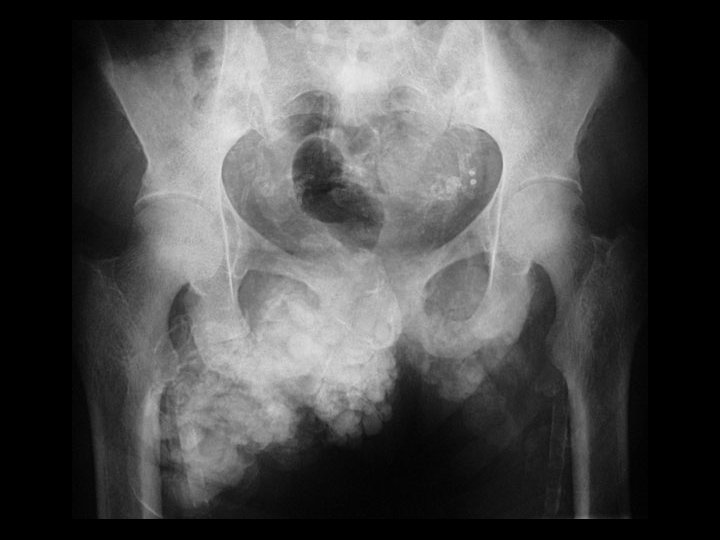

Hyperparathyroidism & Dystrophic soft tissue Ca+ • Findings: – Abnormal soft tissue Ca 2+ in the anterior pelvis – Vascular Ca 2+ • ddx: – Tumoral calcification – Myositis ossificans progressiva

ESRD & amyloid arthropathy • Findings: – Osteopenia and fuzzy trabecula = osteomalacia – erosions on both sides of the hips joints – multiple joint involvement • ddx: (single joint) – synovial chondromatosis – PVNS